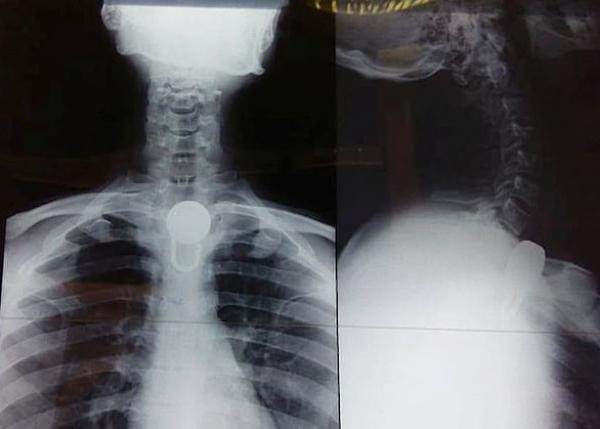

شاب هندي يعاني من مشاكل عقلية يبتلع قفلاً .. فيضطر لإجراء عملية جراحية